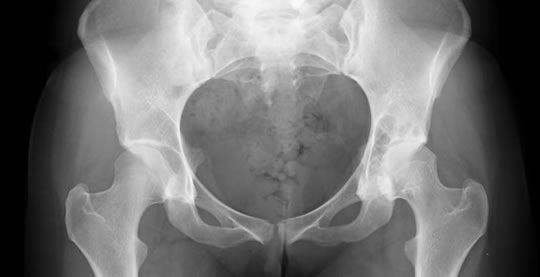

Tratamos no solamente lesiones traumáticas, deportivas, de accidentes laborales, de tránsito, etc. sino también todo tipo de enfermedades del aparato osteo-articular, incluyendo deformidades congénitas como luxaciones de cadera, deformidades de los pies, manos, rodillas; enfermedades de la columna como escoliosis congénita o adquirida, enfermedades degenerativas de las articulaciones como artrosis de cadera y de rodilla especialmente.

Para todos estos tratamientos utilizamos múltiples métodos tanto ortopédicos como quirúrgicos, llegando de esta manera al recambio articular en el caso de prótesis de rodilla, cadera, hombro, etc.